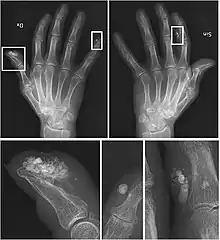

CREST causes thickening and tightening of the skin with deposition of calcific nodules ("calcinosis").

Sclerodactyly

Though it is the most easily recognizable manifestation, it is not prominent in all patients. Thickening generally only involves the skin of the fingers distal to the metacarpophalangeal joints in CREST. Early in the course of the disease, the skin may appear edematous and inflamed. Eventually, dermal fibroblasts overproduce extracellular matrix leading to increased tissue collagen deposition in the skin. Collagen cross-linking then causes a progressive skin tightening. Digital ischemic ulcers commonly form on the distal fingers in 30-50% of patients.[3]